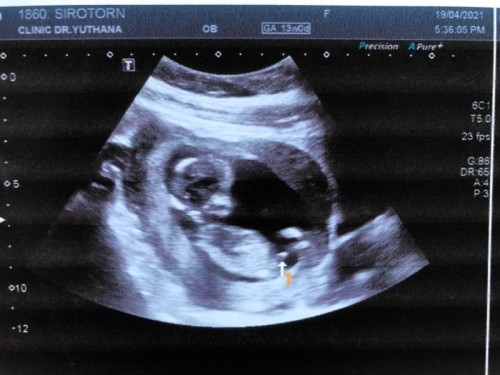

ตอนนี้น้อง 13 w แล้วค่ะ อยากทราบว่าเป็นไปได้ไหมที่จะเห็นเพศชัดตั้งแต่ตอนนี้ คุณหมอบอกว่ามีโอกาสได้ผู้ชายค่ะ แต่ที่บ้านบอกน่าจะสายสะดือของน้อง

ชายค่ะตามที่หมอชี้เลย ขาวๆเล็กๆ ไม่ใช่ยาวๆนั่นขา